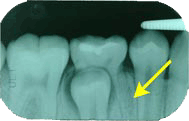

乳臼歯の根は上の乳臼歯で3本、下の乳臼歯で2本あります。乳歯と言えども乳臼歯の根はしっかりとあごの骨の中で広がっています。永久歯が真下から真っ直ぐに上がってくる(萌出する)場合には乳臼歯の根も自然と溶けてしまいグラグラして抜けてしまいます。しかし左のレントゲンのように根(矢印)が残ってしまう場合があります。

左のレントゲンの乳歯を抜いたものです。こんなに長く根が残っていました。これではグラグラするはずがありません。乳臼歯、特に奥の方の乳臼歯(第2乳臼歯)ではよく起こることです。